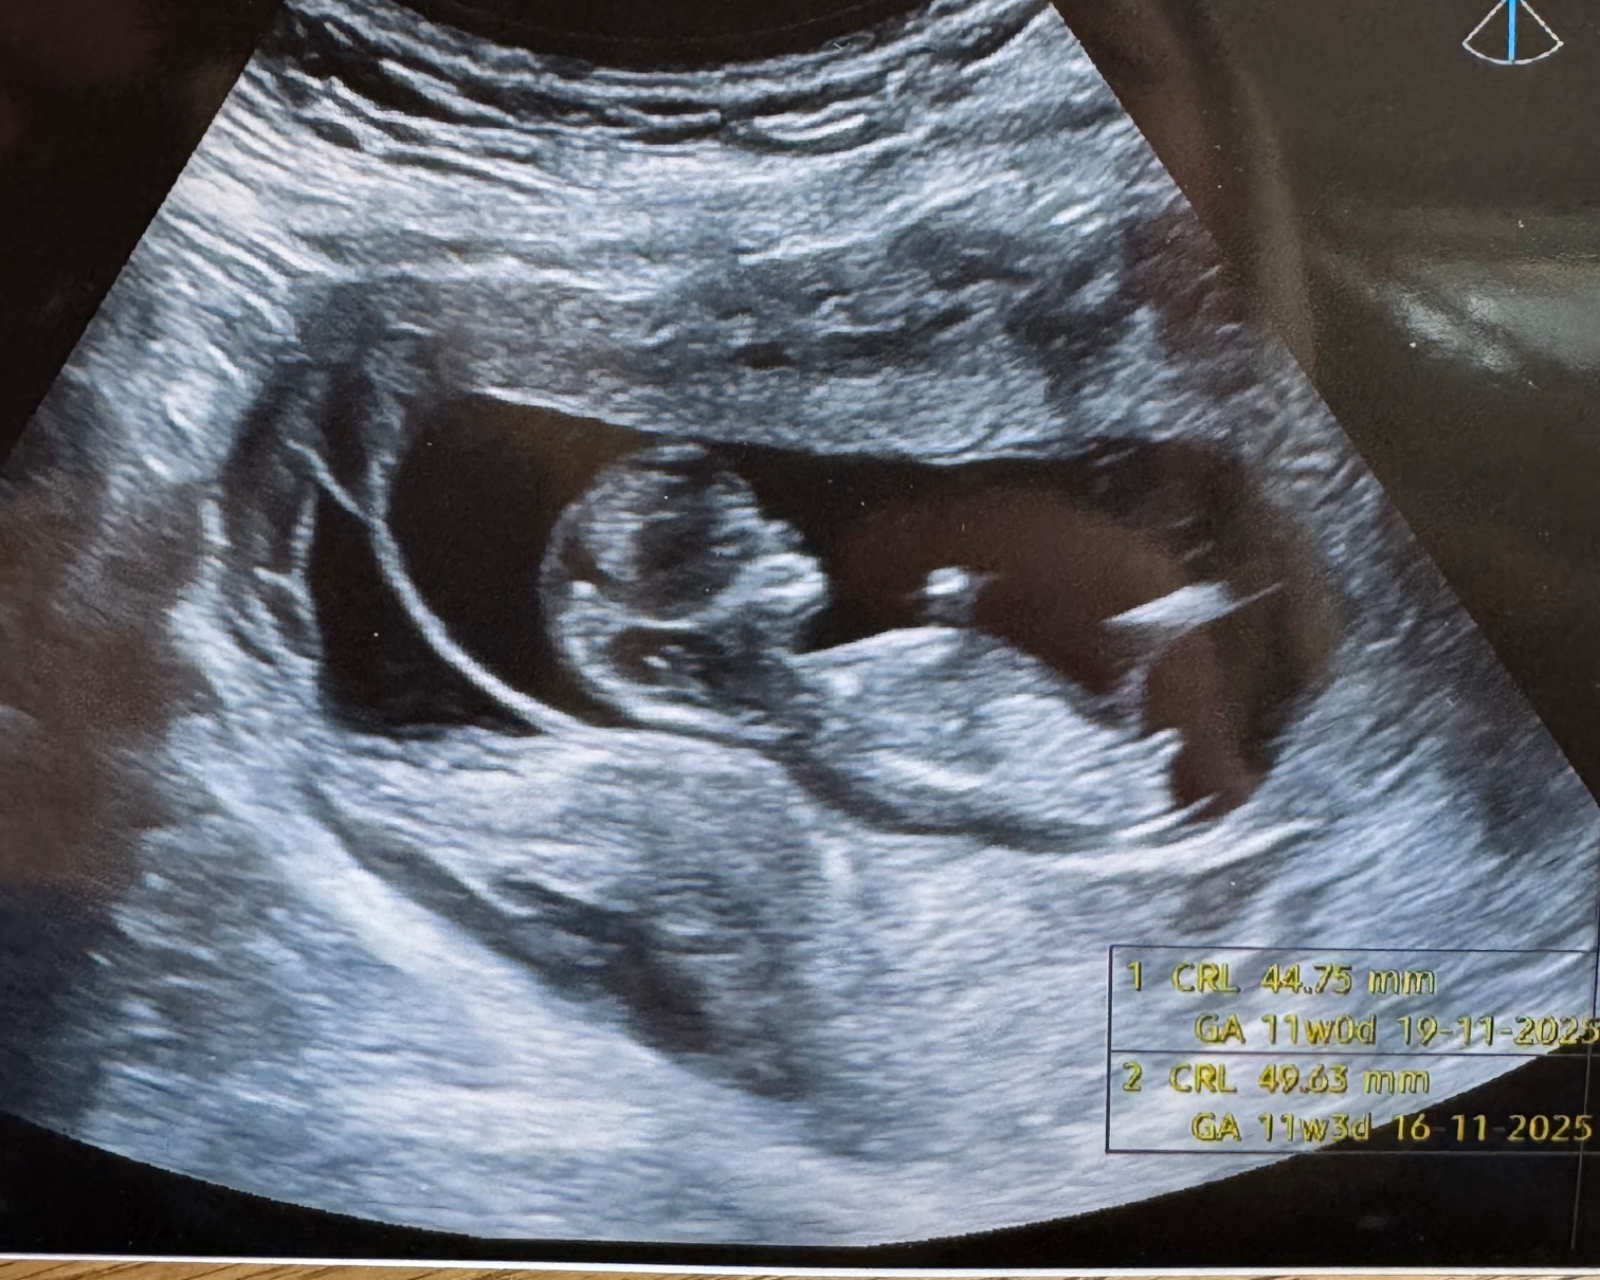

Může někdo určit pohlaví podle ultrazvuku ve 13+3 týdnu?

Prosím co by jste řekli u mě? 😁

Mě přijde, ze holka.

@ovesova taky bych řekla, ze holka... vypadá to stejně jako z naseho UZ ve 14tt 😃

@markeetaaa24 kluk. To pod pupečníkem trčí nahoru 😉

@hollynka myslim si, ze holka 🤗